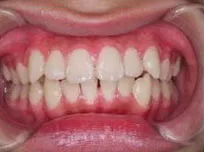

以下、当院で実施した床矯正の症例となります。

症例1

| 治療期間 | 11ヶ月(2021年6月〜2022年5月) |

| 費用 | 495,000円(税込) |

| リスクや副作用 | 成長期が終わった18歳以降に、2期矯正が必要になることがある |